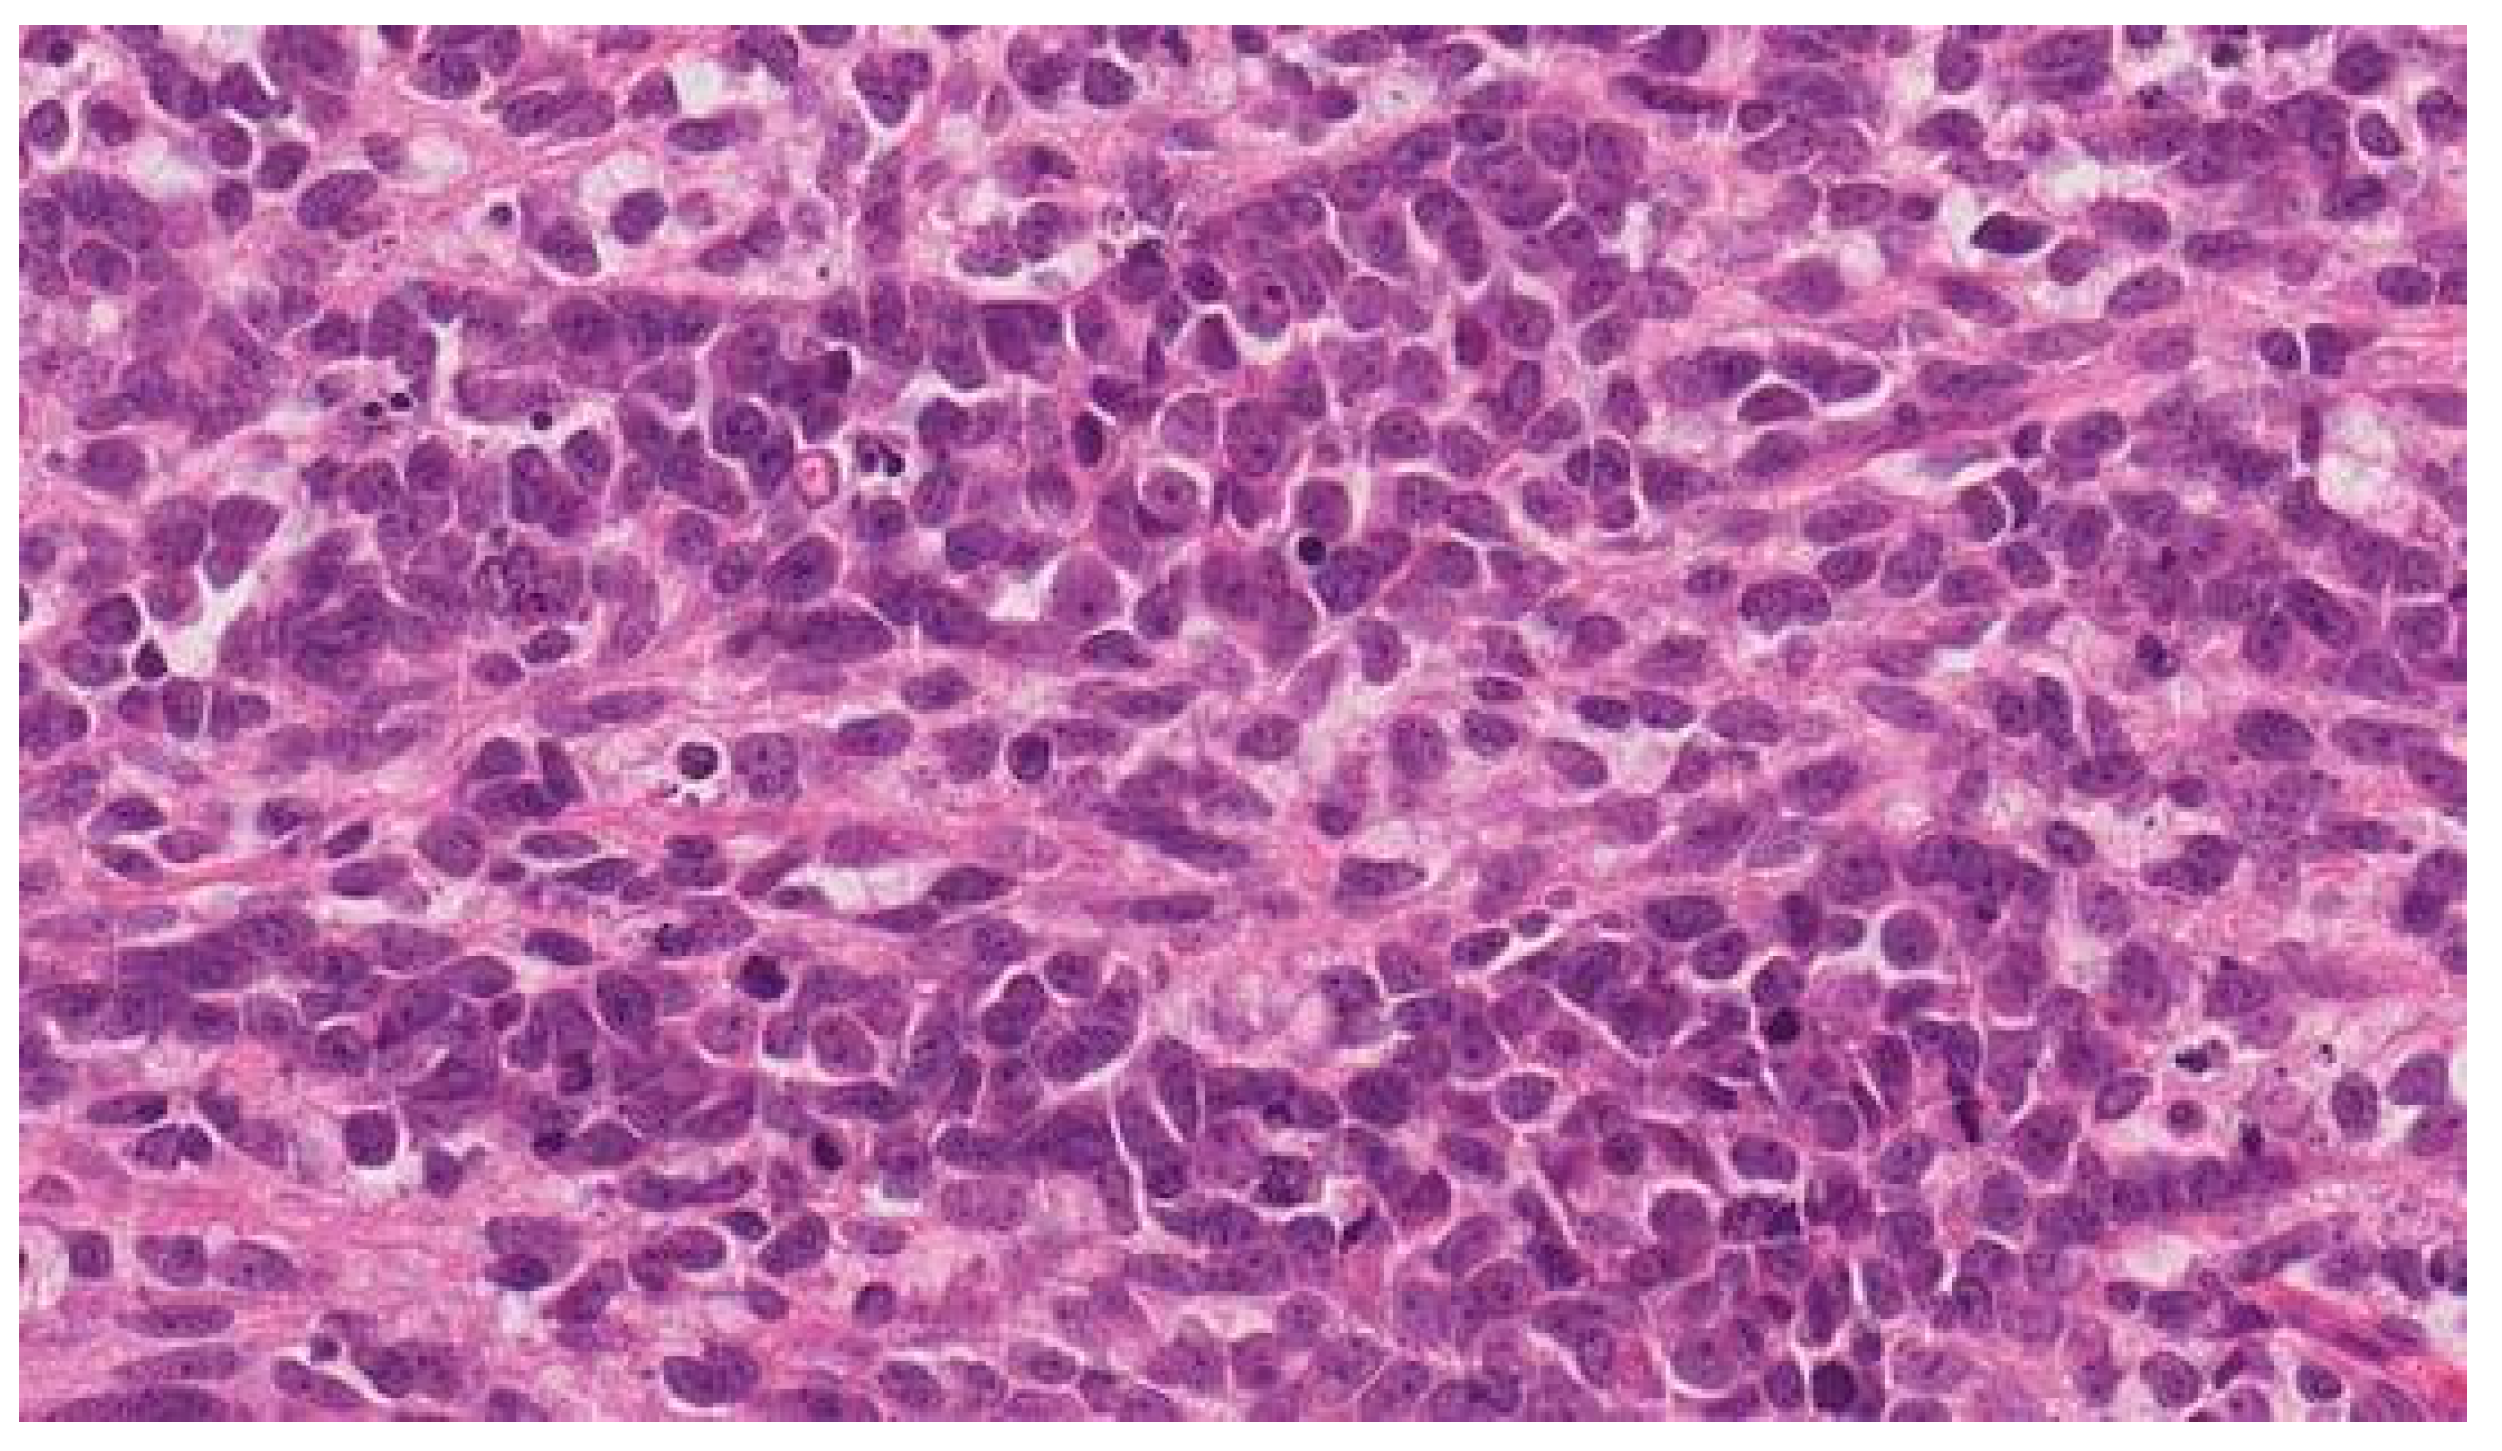

Multiple Rare Primary Malignancies: A Mixed Squamous Neuroendocrine Adenocarcinoma of the Cervix, Metastasized Carcinosarcoma and Extramammary Vulvar Paget’s Disease Case Report

2. Case Report